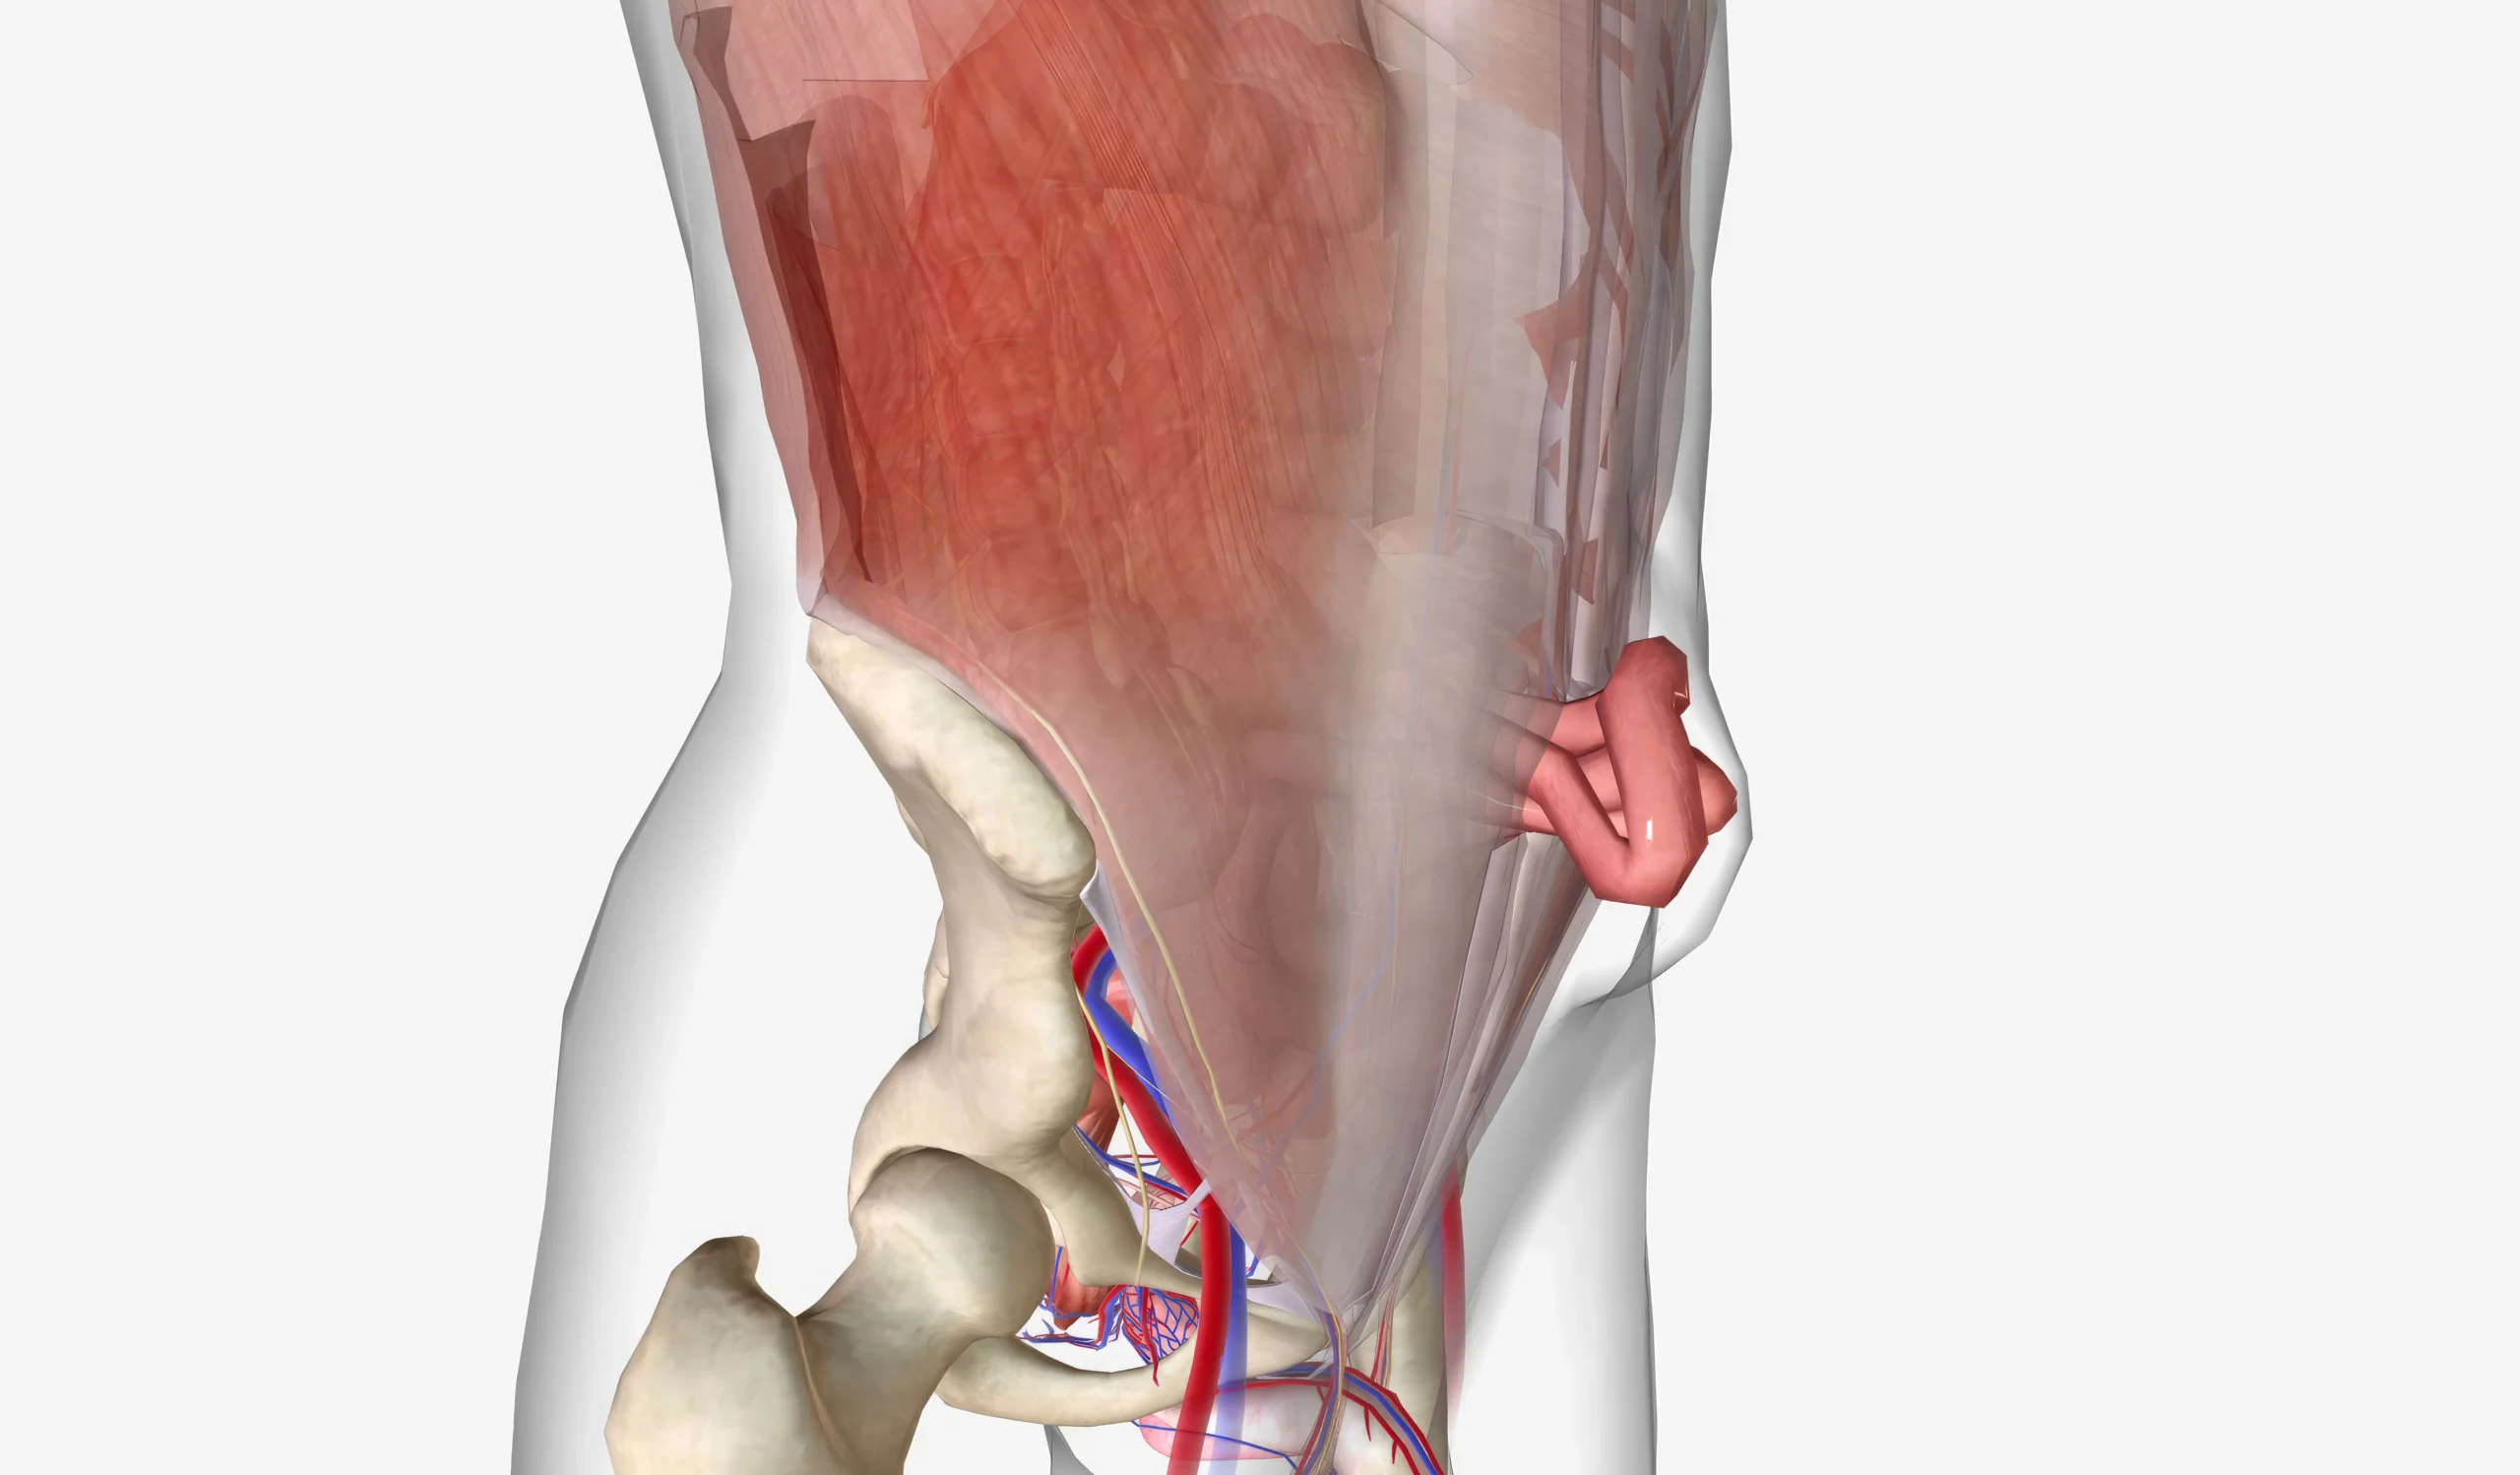

عملية الفتق بالمنظار في عمان او جراحة الفتق في الاردن تُعد خيارًا جراحيًا متقدمًا لعلاج بروز جزء من الأنسجة أو الأمعاء عبر نقطة ضعف في جدار البطن. وغالبًا، يظهر الفتق على شكل انتفاخ يزداد مع الوقوف أو السعال أو حمل الأوزان. كما قد يسبب ألمًا أو شعورًا بالثقل وعدم الارتياح. ولأن درجات الفتق تختلف من شخص لآخر، فإن التقييم الطبي الدقيق يحدد نوع الفتق وخطة العلاج الأنسب، وبالتالي يساعد على اختيار الإجراء الأكثر أمانًا وفعالية لكل حالة

1 – الفتق الإربي (الأربي)

تُجرى جراحة الفتق في الاردن عبر فتحات صغيرة باستخدام المنظار، ويتم إصلاح نقطة الضعف وتقوية جدار البطن، وغالبًا يتم دعم الإصلاح بشبكة (Mesh) وفق ما يراه الطبيب مناسبًا للحالة.